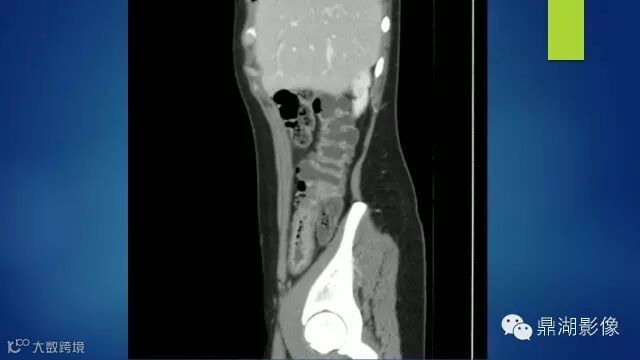

do you know comb sign?

The comb sign refers to the hypervascular appearance of the mesentery in active Crohn disease.